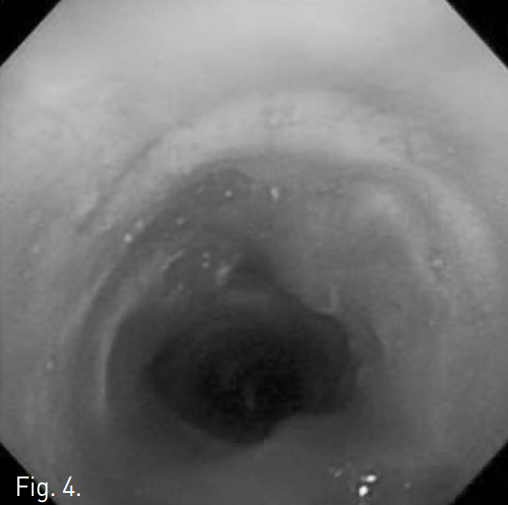

Laryngeal CT에서 vocal cord 하방 4 cm 위치에 수 mm 길이를 갖는 focal tracheal stenosis가 있으며 동반된 mural thickening이 있었음. Virtual bronchoscopy를 통한 3D reconstruction image에서 해당 병변의 위치 및 협착의 정도를 평가할 수 있음(Fig. 1). 기관지 내시경에서 병변 주변 점막의 충혈이 있었고 web-like luminal stenosis가 있음(Fig. 2).

Fig. 1

A, B. 3D reconstruction images with virtual bronchoscopy show focal tight tracheal stenosis.